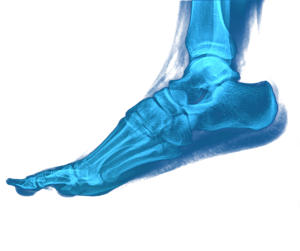

In terms of the foot and ankle injuries, lateral ankle ligament sprains and injuries are the most common, followed by Achilles tendon injuries. Like rugby, football is a highly demanding, multi-directional sport.

This increase is in solid bone and muscle. The problem is that the ligaments and tendons that hold these bones and muscles together have not got any bigger or stronger during those four decades and this leaves rugby players vulnerable to tearing these tissues.

Proprioception means, for example, adjusting your balance when you change direction, in order to avoid an ankle sprain. But too often, particularly at lower levels of the game, the focus is overwhelmingly upon building strength and speed, producing players who are increasingly large and vulnerable to injury.